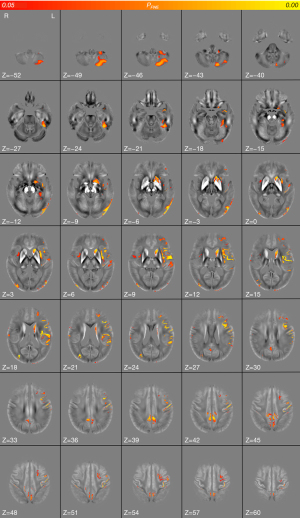

Whole-brain cross-sectional analysis revealed that relative to the HCs, the AD group had widespread increased absolute susceptibility along the cortical ribbon, predominantly in the left cerebral cortex, which reflected increased iron content. Abnormalities on the left side were found in frontal lobe structures including the superior frontal gyrus, middle frontal gyrus, inferior frontal gyrus, frontal pole, and precentral gyrus; in parietal lobe structures encompassing the precuneus cortex, postcentral gyrus, supramarginal gyrus, and angular gyrus; in temporal lobe structures including the inferior temporal gyrus, middle temporal gyrus, fusiform gyrus, and parahippocampal gyrus; in occipital lobe structures, primarily the lateral occipital cortex and occipital pole; and in the insula cortex, opercular cortex, and cingulate cortex (P<0.05, FWE-corrected). Deep gray matter nuclei located in the basal ganglia, including the left caudate and putamen nuclei, were also found to be involved. In the AD group, although absolute susceptibility was primarily increased in the left cerebral cortex, extensively covering the left frontal, parietal, temporal, and occipital lobes, the right cerebral cortex also had relatively sparse regions with abnormally increased absolute susceptibility, including the right precuneus cortex, cingulate gyrus, lateral occipital cortex, occipital pole, insular cortex, opercular cortex, postcentral gyrus, precentral cortex, and supramarginal gyrus (P<0.05, FWE-corrected). Notably, the susceptibility of the Crus II, VIIb, and VIIIa regions in the left cerebellar cortex was also significantly increased in the AD group (P<0.05, FWE-corrected). No significant clusters of decreased absolute QSM values were found in the AD group. The peak MNI coordinates and anatomical labeling of significant clusters with increased absolute susceptibility are presented in Table 2 and Figure 3, respectively.

Whole-brain QSM regression analysis with cognition showed that, in patients with AD, increased absolute susceptibility in the right angular gyrus, supramarginal gyrus, lateral occipital cortex, parietal operculum cortex, left frontal operculum cortex, and inferior frontal gyrus was associated with decreased MMSE scores (Figure 4A; Table 3; TFCE, FWE-corrected P<0.05). Increased susceptibility in the right angular gyrus, supramarginal gyrus, lateral occipital cortex, superior temporal gyrus, left superior frontal gyrus, inferior frontal gyrus, and frontal pole was also associated with decreased MoCA scores in patients with AD (Figure 4B; Table 3; TFCE, FWE-corrected P<0.05). Interestingly, similar patterns were seen in maps of whole-brain QSM regression analysis plotted against MoCA scores and against MMSE scores. However, unlike those of cross-sectional analysis, the results of QSM regression analysis with cognition were primarily located in the right hemisphere.